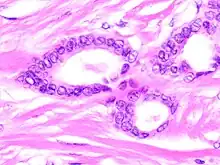

Histopathology of tubular carcinoma, low magnification, H&E stain. It shows the typical features of invasive breast cancer with infiltrative growth pattern, here including invasion into adipose tissue and with an associated fibrous or desmoplastic stromal response. It has the criterion of more than 90% of the tumor composed of small, ovoid or angulated tubules with open lumina. Ductal carcinoma in situ is seen at left as lumina with micropapillary formations (under the larger bland cyst), and was presumably the precursor lesion for the ductal carcinoma.[1]

Tubular carcinomas are generally around 1 cm. or smaller, and are made up of tubules. They are usually low-grade.[2] Elastosis has been noted as common but is not present in all cases.[11]